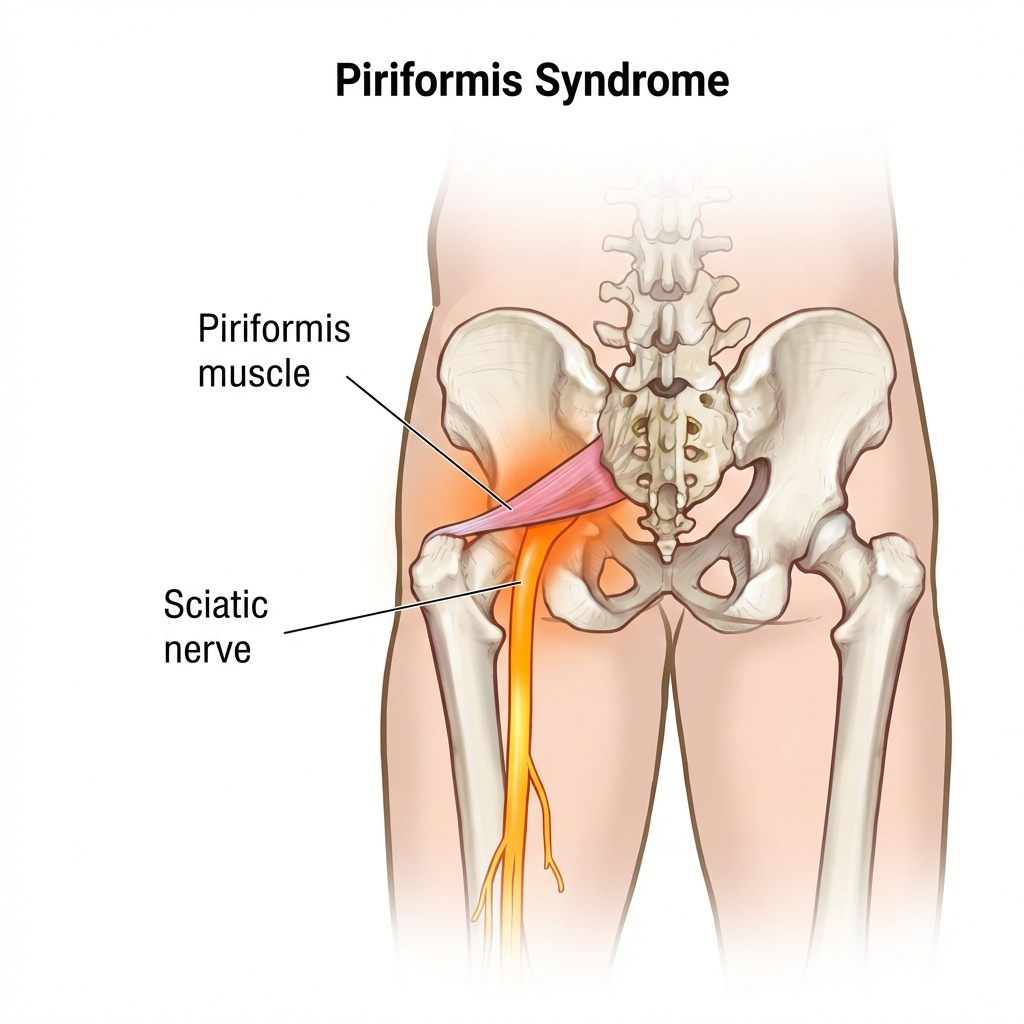

Piriformis Syndrome

What is the piriformis?

A deep muscle in the buttock that lies directly over the sciatic nerve.

What happens

When the piriformis tightens or spasms, it compresses the sciatic nerve, mimicking disc-related sciatica.

Key symptoms

- Deep buttock pain on the right

- Pain radiating down the leg

- Pain worsens with sitting or driving

- Minimal or normal MRI findings

Why it’s missed

Standard scans may appear normal—diagnosis is largely clinical.